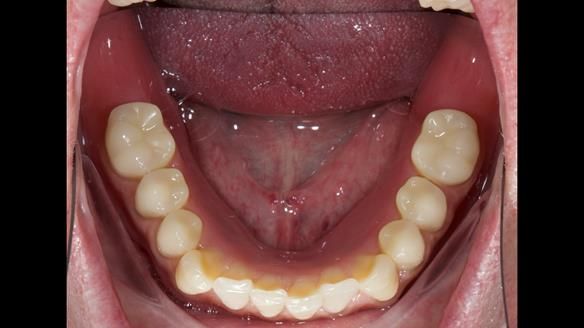

Welcome to my Newsletter 57, where I show the making and fitting of complete dentures supported by upper and lower dental implants for Alisdair. This issue provides a comprehensive overview of the entire protocol workflow.

3. Both upper and lower dentures can be enhanced in appearance.

The detailed clinical situation and treatment process are outlined below, with clinical work provided by me and technical work by Rowan Garstang. New complete implant supported complete dentures were made. The new upper denture had ‘almost’ full palatal extension for the non-splinted implants following ITI guidelines. A decision was reached to retain the worn Kerator attachments, as their removal could potentially accelerate implant failure. The treatment spanned five visits for denture fitting and one review. Alisdair expressed great satisfaction with the treatment, noting a significant enhancement in his overall quality of life.